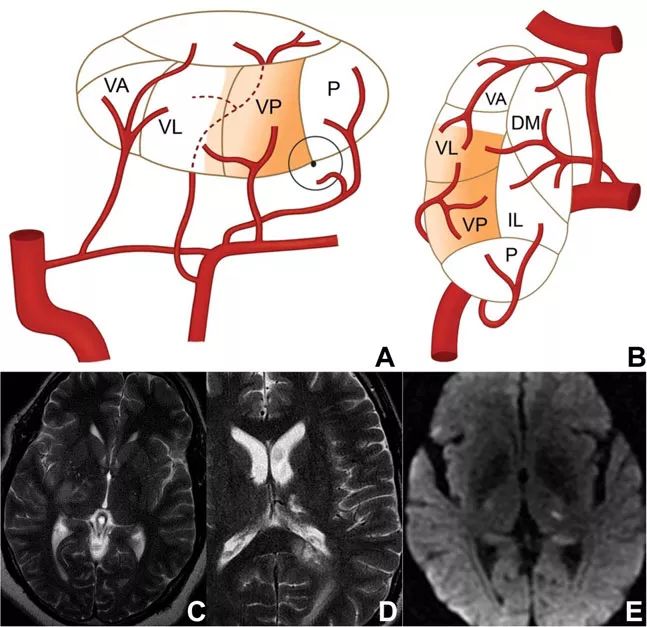

图5 丘脑旁正中动脉供血示意图和梗死影像学表现

丘脑旁正中动脉梗死的症状取决于血管变异的类型,可能为单侧或双侧。对于单侧旁正中动脉梗死的患者,早期阶段主要表现为兴奋程度减弱和意识水平波动,可持续数小时至数天。长远上看,情绪和行为变化依然会出现,包括躁动、激越、迷失方向、冷漠等。左侧的梗死也可表现为语言功能障碍。

Percheron动脉闭塞引起的双侧丘脑梗死已得到人们充分认识。这种综合征相对少见,占所有缺血性卒中的7%,典型的症状共包括4点:

➤ 警惕性障碍,如昏迷或木僵;

➤ 明显的记忆障碍,难以产生新的记忆,常有虚构;

➤ 本能和情绪的变化,一般伴有烦躁不安、冷漠或长期呈现不良情绪;

➤ 垂直凝视麻痹,可能没有垂直扫视和追踪动作。

其他临床症状还包括如定向力障碍、意识混乱和无动性缄默症等。大多数患者的神经系统障碍和嗜睡可恢复,但认知缺陷和冷漠症状倾向于更为严重且持久。